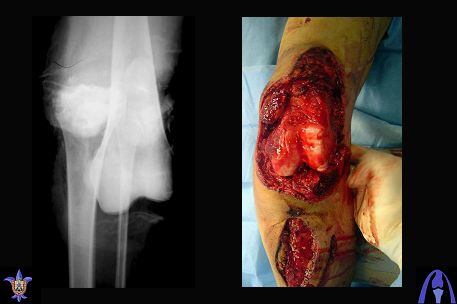

Bolnoi 27 let, DTP, Motorcycle trauma, postupil v kreane tiajelom sostoianii, osnovnia trauma- otkrity totalny vivih levogo kolennogo sustava s povrezdeniem malogo bersovogo nerva, tracionnoi povrezdenia podkolennoi arterii bez narushenia selostnost' sosuda, pomosh' okazanno v nujnum obmeme, kakoe ze mnenie uvazaemih kolleg naschet dalneshego vvedenia bolnogo? Castro

Uvajaemiy kollega! *Pomosh okazano v nujnom ob`eme*- kak ponyat? Vosstanovili krestoobraznih i bokovih svyazok? ili prosto vivih vpravili i fiksirovali AVF. sudya po R-snimkam nadkolennik nahoditsya visoko- znachit povrejdena i sobstvennaya svyazka, kotoraya ne ushita. Potom mojno sostavit plan lecheniya. S uvajeniem Abdurashid.

Доктор Castro,

На ренгенограмме хорошая аппозиция костей коленного сустава, но надколенник находится подозрительно высоко, поэтому необходимо убедиться в отсутствии повреждения связки надколенника.

Снимки прошлых публикации из моего Power point